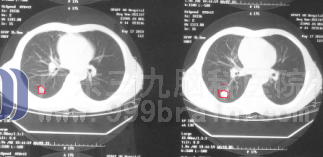

来自广东河源的阿美今年四十四岁,因为婚姻的失败,在情绪低落、心情烦躁时经常接连不断抽闷烟,烟龄近10年,家人的劝解也从来不听。今年8月初阿美出现咳嗽症状,刚开始以为是感冒,没放在心上,以感冒止咳治疗后没有好转,还出现胸痛。一月后检查X线示右肺有阴影,行纤支镜活检明确病理,病理结果示右肺非小细胞肺癌。医生建议手术,阿美由于自身原因不愿手术,经多方了解后知道非小细胞肺癌通过放化疗效果很好,故9月初来广东三九脑科医院肿瘤综合治疗中心 接受放化疗。放疗至一定剂量后患者已无咳嗽和胸痛,复查CT示肿瘤已明显缩小,继续完成放疗计划剂量。目前放疗后辅助化疗还在进行中,患者情况良好。www.999brain.com

▲治疗前

▲治疗后(肿瘤明显缩小)